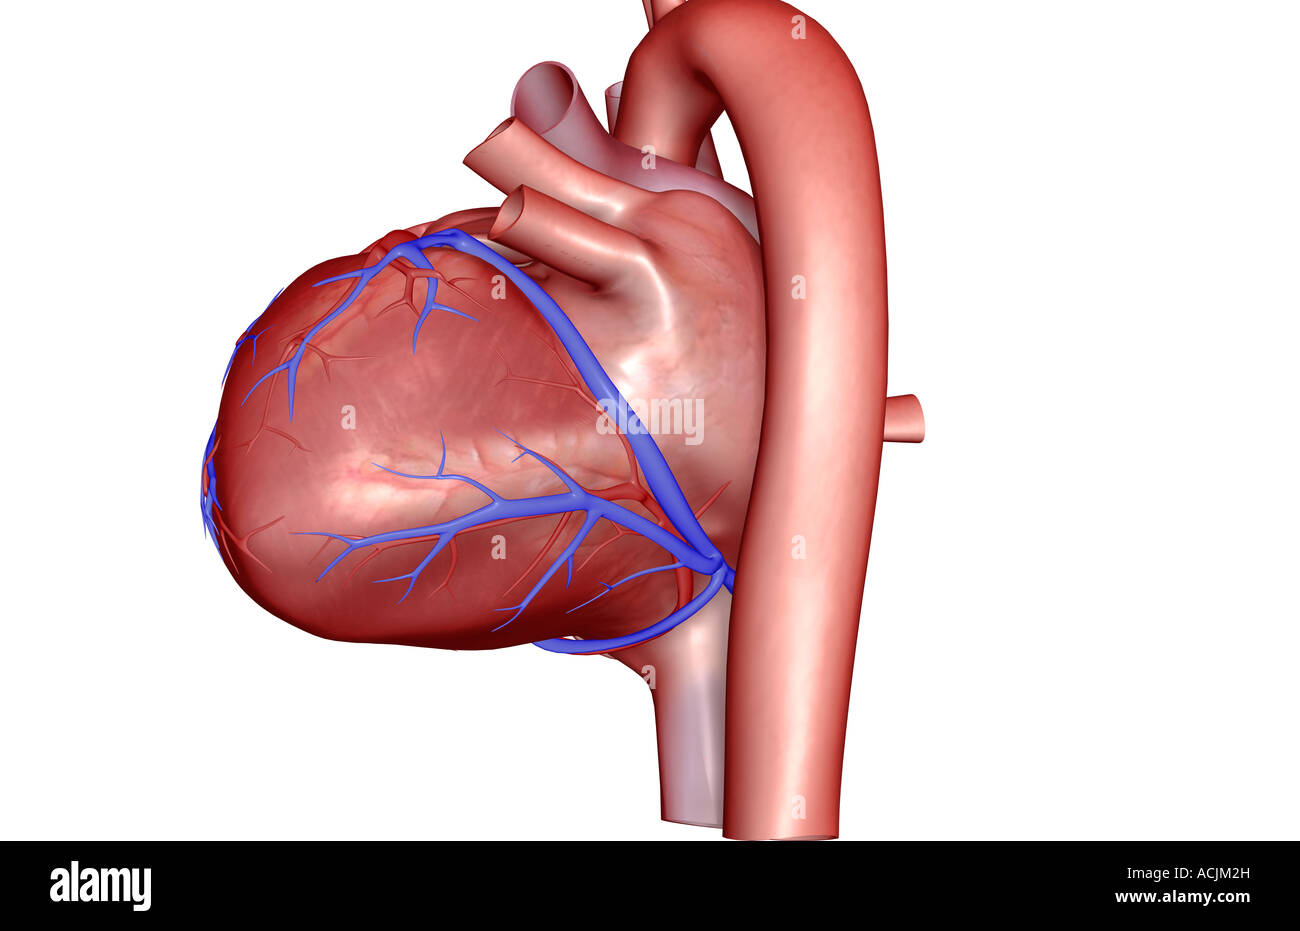

The coronary vessels of the heart Stock Photohttps://www.alamy.com/image-license-details/?v=1https://www.alamy.com/stock-photo-the-coronary-vessels-of-the-heart-13173426.html

The coronary vessels of the heart Stock Photohttps://www.alamy.com/image-license-details/?v=1https://www.alamy.com/stock-photo-the-coronary-vessels-of-the-heart-13173426.htmlRFACJW8K–The coronary vessels of the heart